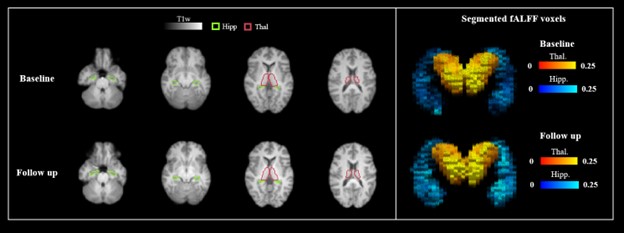

Table 1 summarises the demographic details of participants and their structural/functional MRI readouts (n=274). T statistics does not show a significant difference between the baseline and the follow-up readouts for both fALFF and volume changes in hippocampus and thalamus. Figure 1 shows an example of hippocampus and thalamus segmentation and an example of a calculated fALFF map for one participant. Figure 2 demonstrates a correlation between baseline MRI readouts versus follow-up MRI readouts for both hippocampus and thalamus regions of interest. Strong positive correlations were observed within both hippocampus and thalamus for both volume readout and fALFF readouts, while fALFF model prediction (R2 ~ 0.2) shows more variability when comparing with volume prediction (R2 ~ 0.8). Table 2 presents the summary of multivariable linear modeling using Model 1 and Model 2. We found strong correlations between baseline and follow-up MRI readouts within all linear models. We also found a trend showing baseline mean fALFF is positively correlated with follow-up volume change within thalamus ROI (P=0.053) with a relatively sizeable R2 value. Given baseline hippocampal volume, age strongly predicts follow-up hippocampal volume. Surprisingly, age is not associated with thalamus volume as well as hippocampus/thalamus fALFF.

Figure 1. Left panel shows an example of hippocampus (green) and thalamus (red) segmentation based on T1w MRI images. Right panel shows a 3D voxel representation of hippocampus (blue) and thalamus (yellow) segmentation based on fALFF maps from a UKB participant who showed an increase of 0.02 in mean fALFF within hippocampus region of interest. Hipp: Hippocampus, Thal: Thalamus.